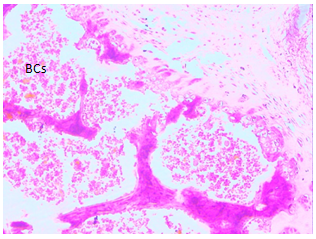

In the research sections of the bone marrow displays an epiphysis along with bone marrow blast at various levels of maturation which are separated with spikes of bone. From inside the marrow tissue there are a few megakaryocytes associated adipocytes were also seen. These features are in accordance with mild bone marrow hypoplasia following the administration of paraquat administration on day 7 (Figure 3 and 4). Although, at day 21, the section of bone marrow tissue is seen to be composed of bone tissue including developing blood cells at various stages of development although cell lines in which sparse and adipocytes remain scant (Figure 5 and 6) compared to the control group (Figure 1 and 2). Such characteristics are consistent with moderate bone marrow tissues. On day 42, sections of bone marrow display the bone tissue along with associated marrow in which are scant blast cells. There exists an abundance of spaces separated by bone spikes. These features are in line with bone marrow failure (severe bone marrow hypoplasia) (Figure 7 and 8).

Figure 1 Bone Marrow Biopsy (Control) H & E x 40.

Figure 2 Bone Marrow Biopsy (Control) H & E x 100.

Figure 3 Bone Marrow Biopsy (Day 7) H & E (x40).

Figure 4 Bone Marrow Biopsy (Day 7) H & E (x100).

Figure 5 Bone Marrow Biopsy (Day 21) H & E (x40).

Figure 6 Bone Marrow Biopsy (Day 21) H & E (x100).

Figure 7 Bone Marrow Biopsy (Day 42) H & E (x40).

Figure 8 Bone Marrow Biopsy (Day 42) H & E (x100).

Keys: Bs, bone spikes; Dbc, developing blast cells; AD, adipocytes; BCs, blast cells.